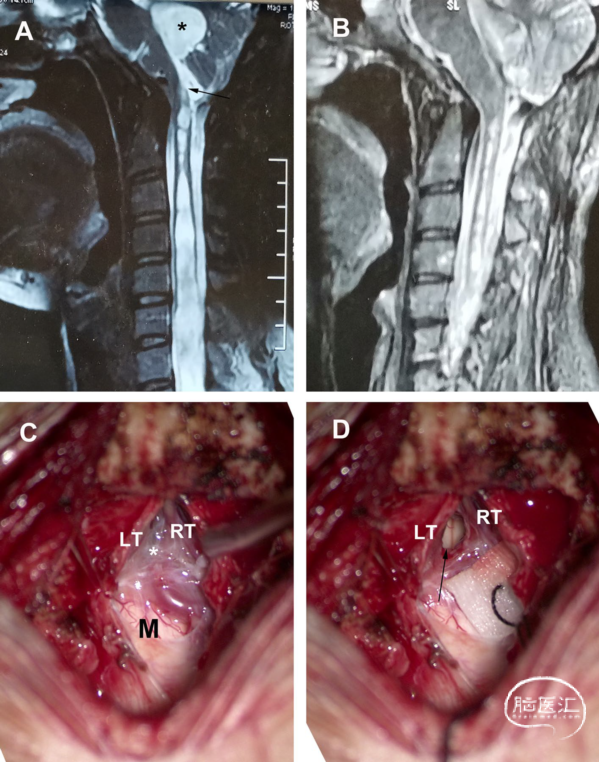

女性,32岁,有1年的枕部疼痛和左肢麻木病史。术前MRI显示,SM向上延伸至延髓,第四脑室未扩张。后颅窝探查显示,扁桃体居中,占据枕骨大孔,并覆盖Magendie孔。同时观察到一层半透明的膜覆盖在Magendie的孔上。进行软膜下扁桃体切除术,移除蛛网膜隔膜(箭头所示)。术后MRI显示,SM的大小显著减小。术后症状完全缓解(图3)。

图3. 部分交通型CM-SM病例。A. 术前MRI-T2矢状位加权成像。注意SM向上延伸至延髓,无第四脑室扩张。B. 高分辨率MR显示,第四脑室和SM(黑色箭头)之间在一定水平上有一个可检测的通道。C. 术后MRI显示,SM明显减少。D. 硬脑膜切口显示,扁桃体居中,扁桃体占据枕骨大孔,并覆盖Magendie孔。E. 可见Magendie孔,并观察到半透明隔膜(箭头)。F. 进行软膜下扁桃体切除术,并移除蛛网膜隔膜(如箭头所示)。